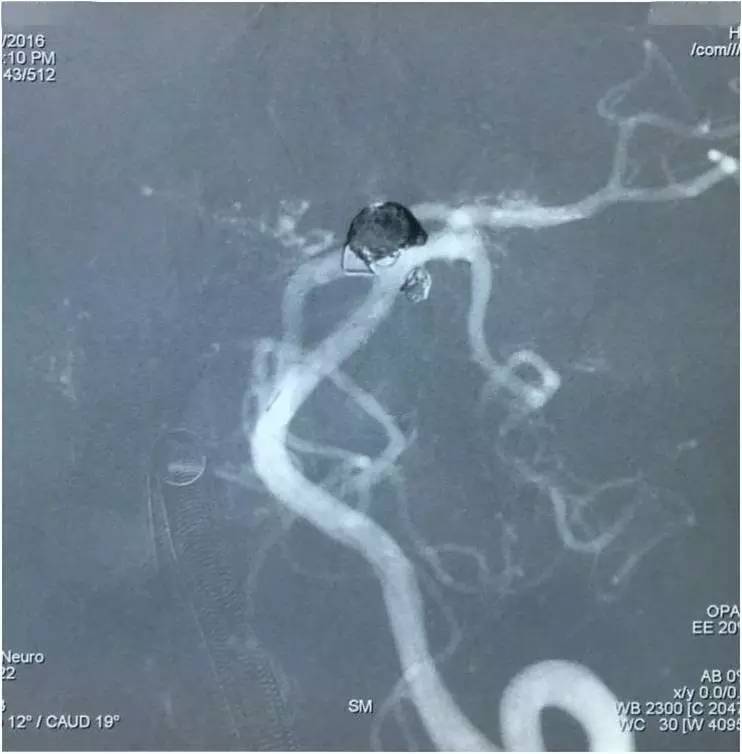

以下图像为DSA,显示基底动脉顶端动脉瘤,左侧小脑上动脉瘤,左侧PCA P1段微小动脉瘤,双侧颈内动脉眼动脉以远闭塞,前循环靠后循环通过后交通动脉代偿。

▼左椎动脉造影正位

▼左椎动脉造影侧位

▼左椎动脉造影三维重建,这个角度可以窥清基底动脉顶端动脉瘤和左小脑上动脉瘤,可见基底动脉顶端动脉瘤顶端的子瘤,考虑是SAH的责任动脉瘤。